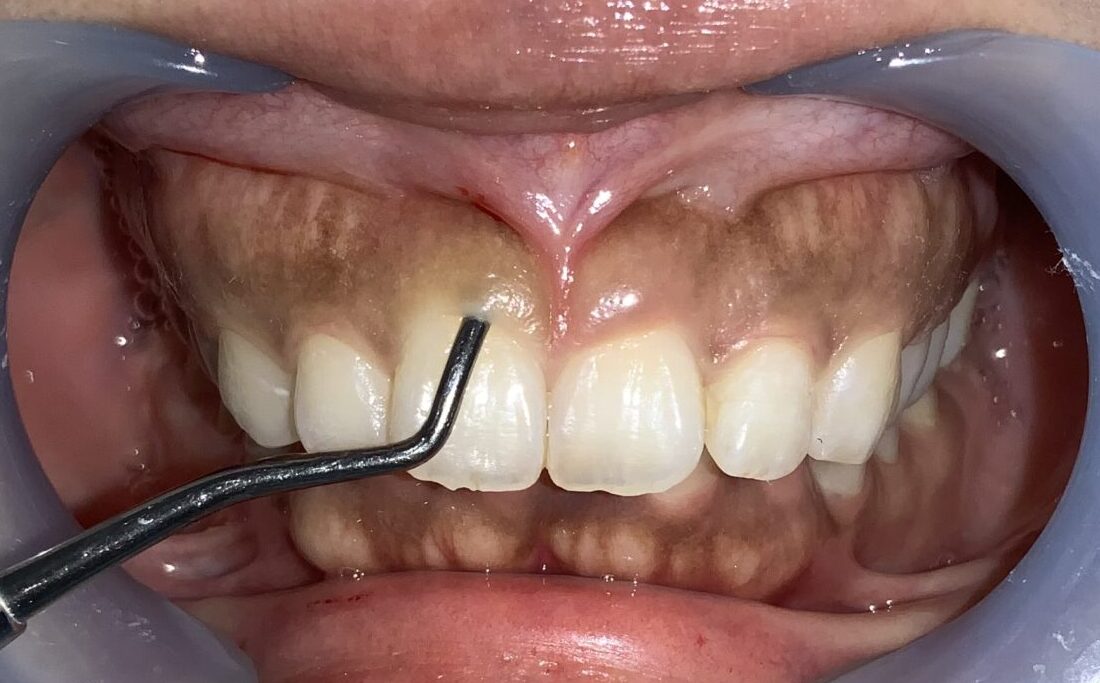

まずは手術前の状態です。

歯に歯ぐきがたくさんかぶっている状態です。

まずは歯ぐきのかぶり具合、歯ぐきの厚み、歯槽骨の状態、歯ぐきの切除範囲の検査からです。

このくらいかぶっていますから、綺麗に切除できます。